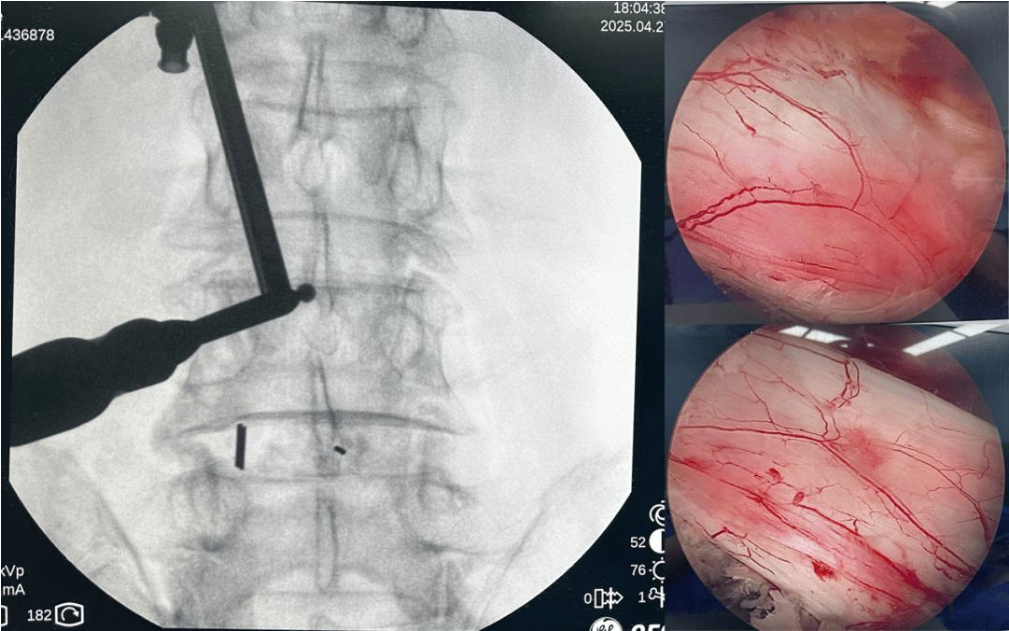

手术过程中,团队凭借丰富经验与默契配合,在UBE内镜清晰视野下,依次对L3-L4、L4-L5节段进行双侧神经减压、间盘切除,并置入椎间融合器与内固定装置,复位滑脱椎体。整个手术操作精细,出血少、损伤小,成功解决了患者双节段的腰椎病变。

术中显示:双节段双侧减压,硬膜囊和双侧神经根压迫解除